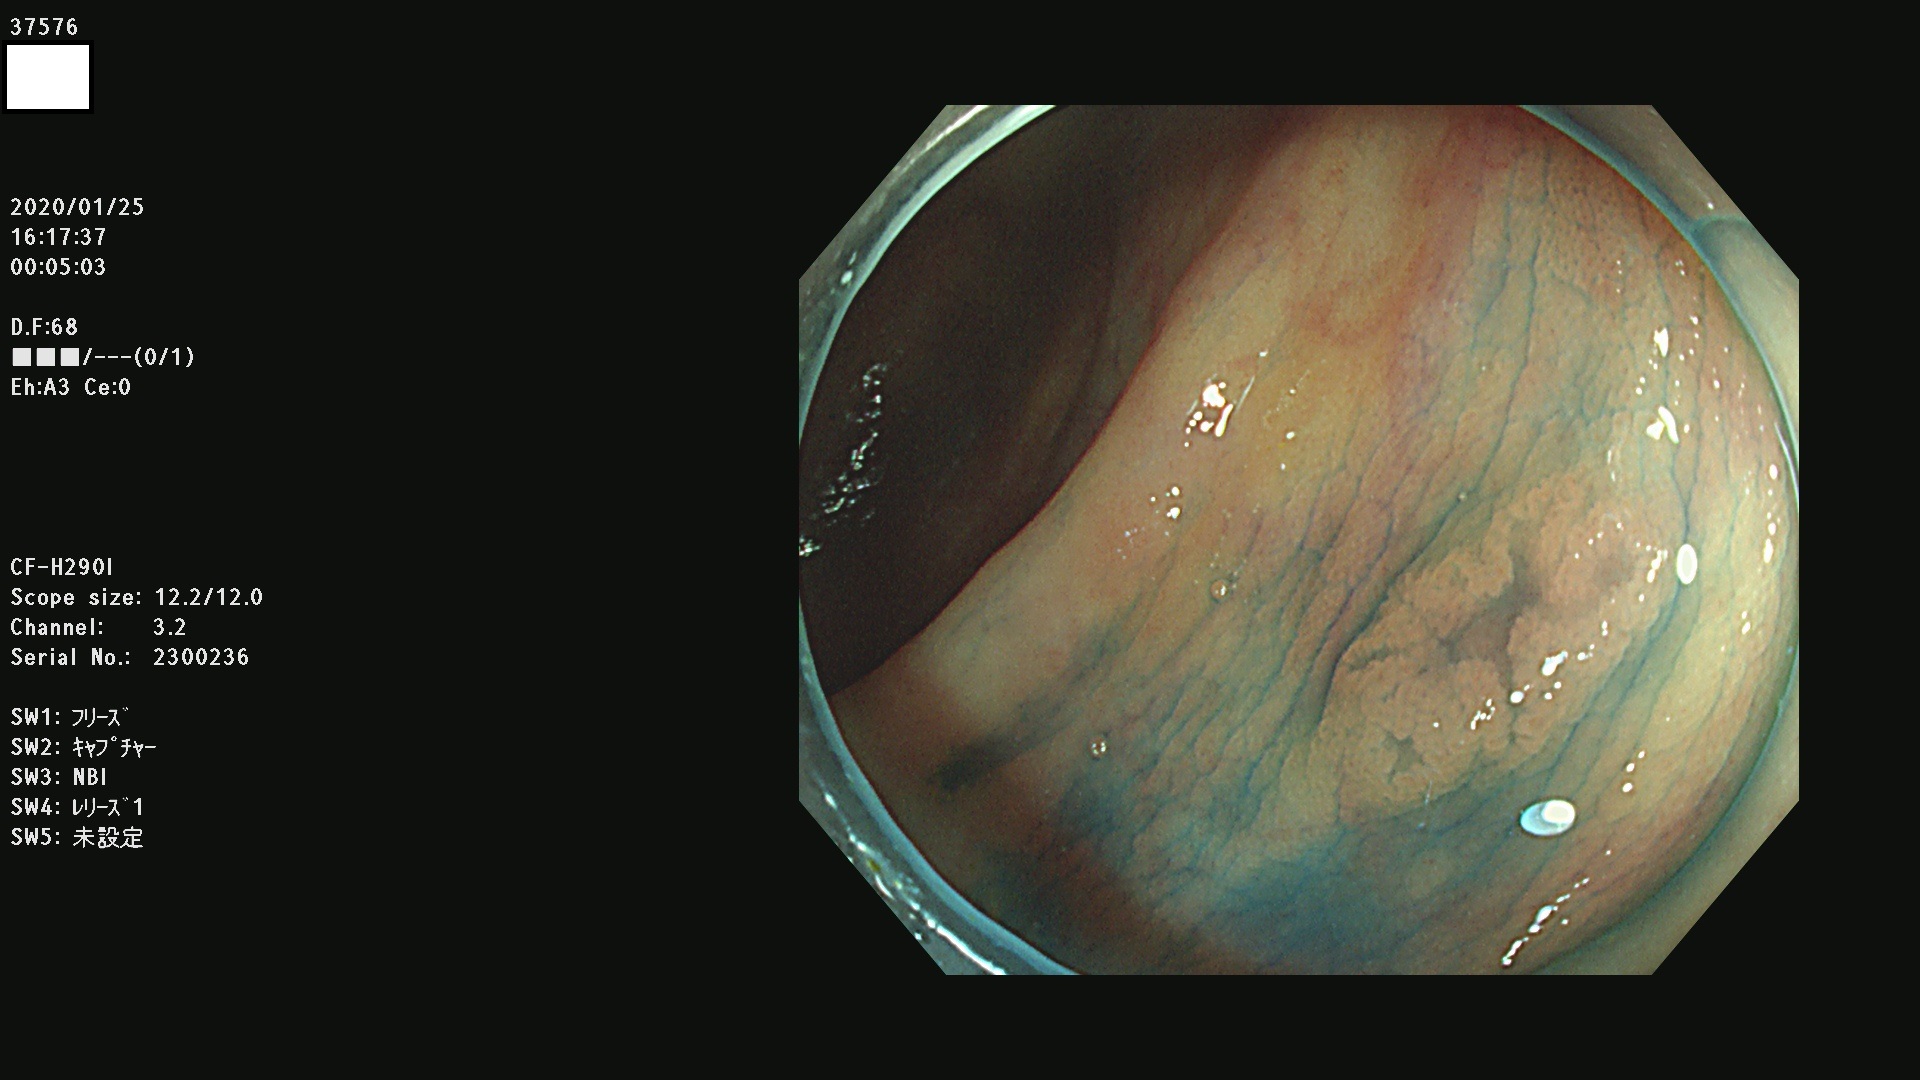

発見困難で危険性の高い平坦型病変(上記100名より抽出) ![]()